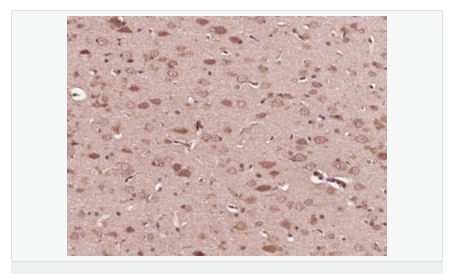

image.png